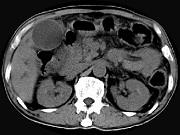

问题 男,58岁,患者右季肋区疼痛,皮肤黄染,可触及肿大胆囊,B超提示胆囊颈部肿块影,CT所见如图,最可能的诊断是()

选项 A.胆囊息肉 B.胆囊癌 C.胆囊黄色肉芽肿 D.慢性胆囊炎 E.胆囊腺肌增生症

答案 B